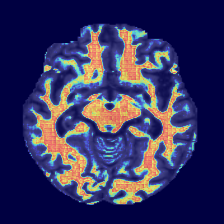

Figure 4: Qualitative comparison of segmentation results on the OASIS-1 and MRBrainS13 datasets. Our proposed PCMambaNet (last column in each set) demonstrates superior performance in boundary delineation and structural coherence compared to several strong baselines. Note our model’s ability to produce segmentations that more faithfully match the ground truth (GT), with noticeably fewer false positives and more accurate handling of complex anatomical regions. Red arrows highlight areas where the advantages of our method are particularly evident.

Qualitative Results. Qualitative results, presented in Figure 4, visually corroborate the quantitative findings and highlight the architectural advantages of PCMambaNet. In the full-data regime (left panel), baseline models often struggle with fine boundaries, producing noisy or incomplete segmentations. In contrast, our model leverages the PPM to focus on critical locations, which then allows the CRN to accurately delineate complex contours that are highly consistent with the ground truth. The superiority of our approach is particularly evident in data-limited conditions (right panel). While competing models yield overly smooth results that miss fine-grained, infiltrative details, our model’s “predict-then-correct” strategy enables it to effectively capture these complex boundary features. Consequently, PCMambaNet produces visually sharper and more anatomically plausible segmentation results, especially in challenging, low-data scenarios.